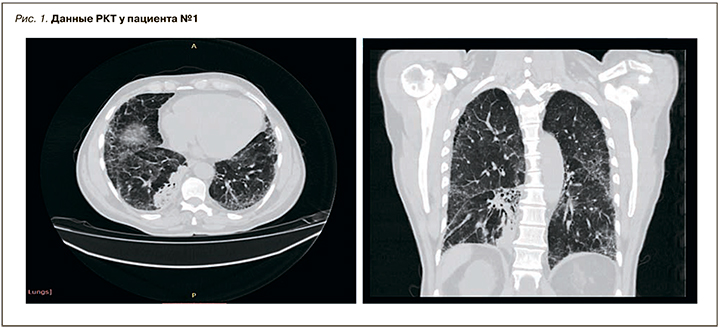

Дальнейшее обследование, включавшее рентгеновскую компьютерную томографию (РКТ) органов грудной клетки, спирографию, подтвердило наличие фиброзирующего альвеолита. По легочным полям с двух сторон на фоне диффузного уплотнения интерстиция в апикальных отделах выявлены многочисленные воздушные полости до 6 мм в диаметре. В проекции S6, S10 правого легкого виден участок интенсивной консолидации с кальцинатами и воздушными полостями до 4 мм. Бронхососудистый рисунок усилен (рис. 1).